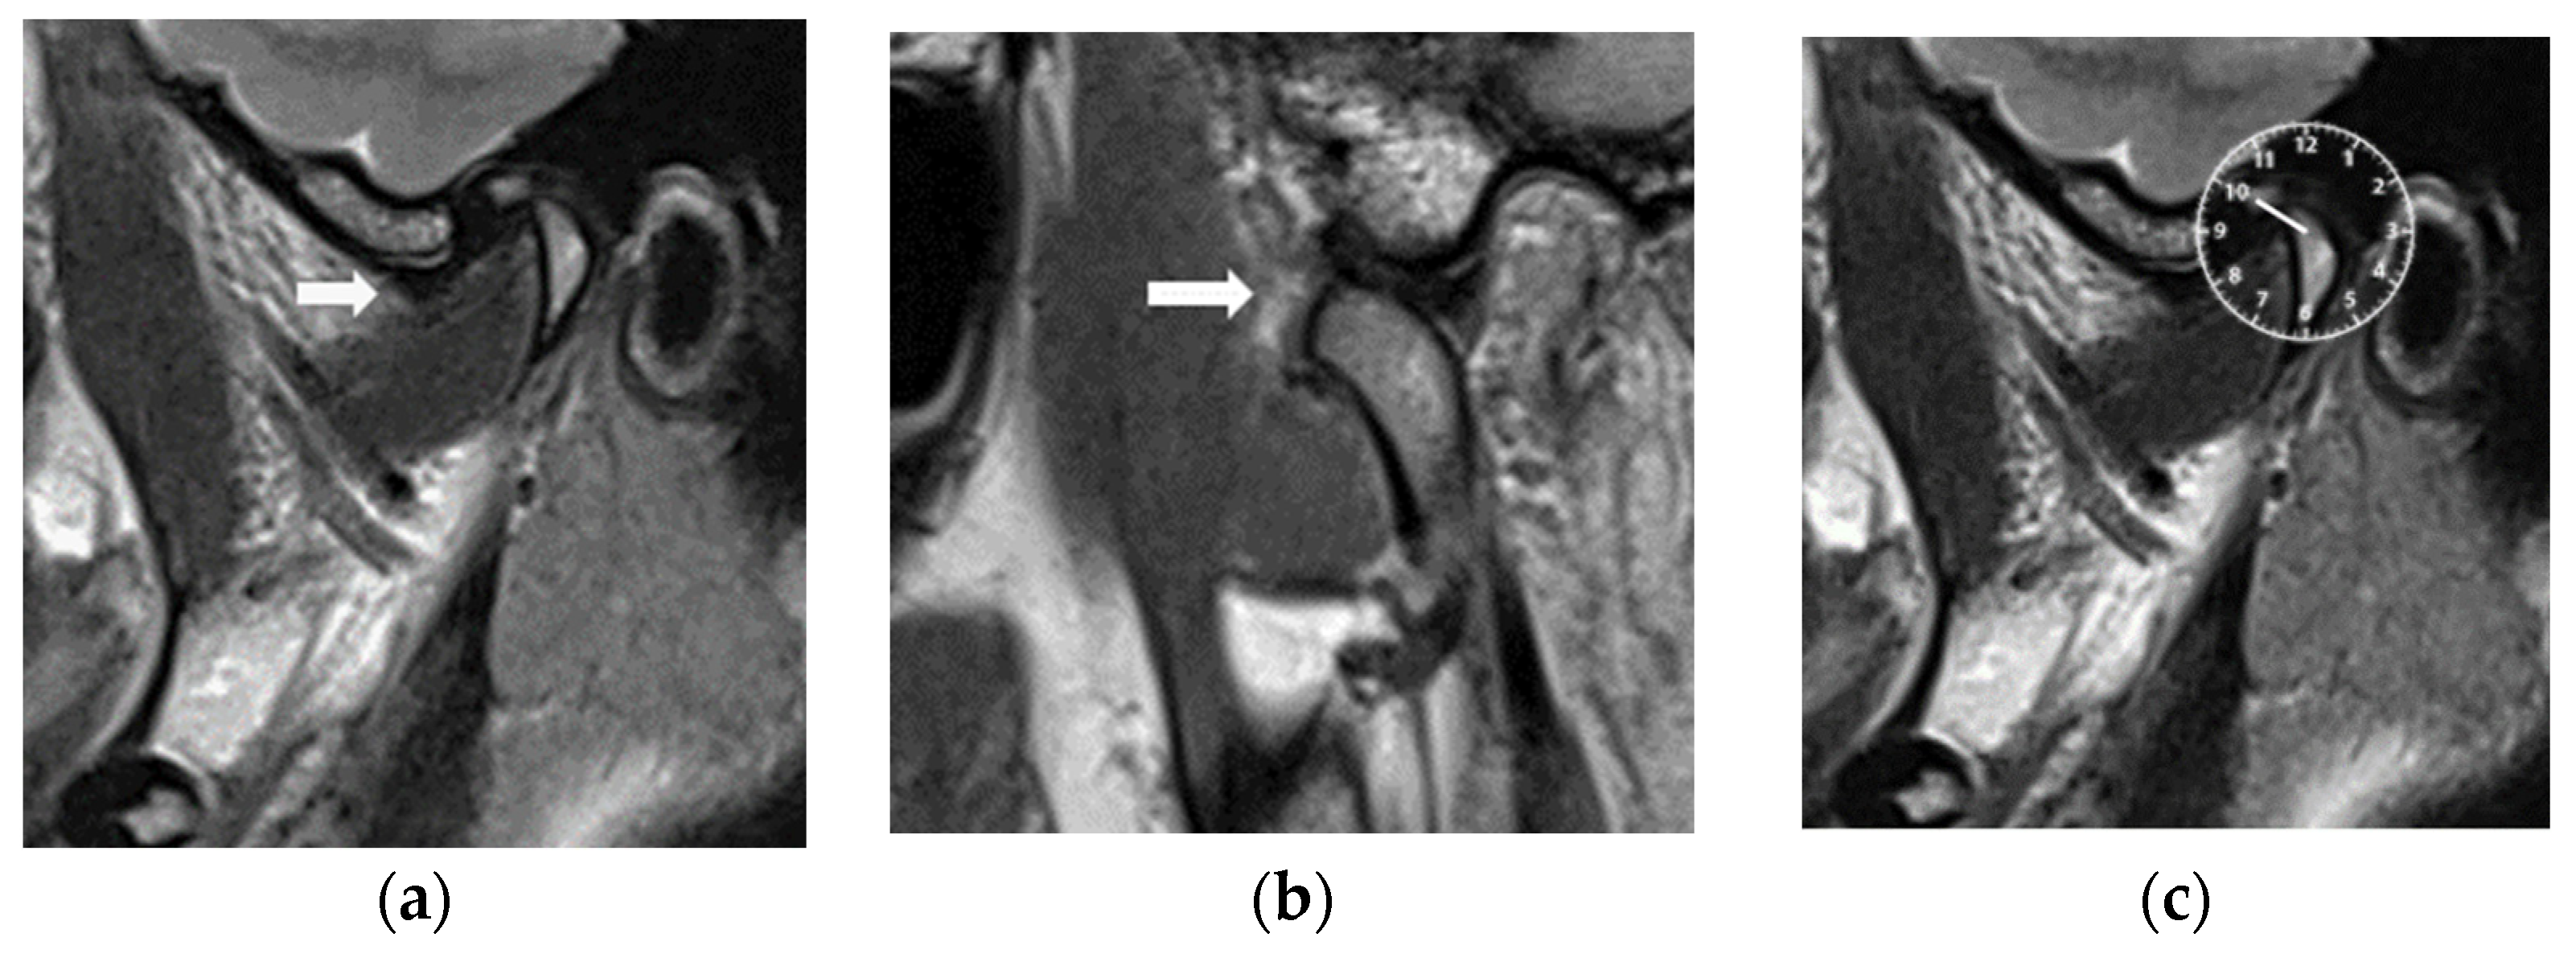

2.2.3. Magnetic Resonance Imaging

| Joint | MRI Slices | Before | After | |||

| Right | 1 | 18 | 10:21 ± 0:30 | 18 | 12:00 ± 0:20 | 0.0002 |

| 2 | 17 | 10:19 ± 0:29 | 18 | 12:01 ± 0:19 | 0.0008 | |

| 3 | 17 | 10:19 ± 0:29 | 17 | 12:03 ± 0:18 | 0.0006 | |

| 4 | 17 | 10:19 ± 0:29 | 17 | 12:03 ± 0:18 | 0.0006 | |

| 5 | 15 | 10:30 ± 0:27 | 16 | 12:03 ± 0:18 | 0.0003 | |

| 6 | 15 | 10:32 ± 0:26 | 16 | 12:03 ± 0:18 | 0.0003 | |

| 7 | 13 | 10:32 ± 0:28 | 15 | 12:04 ± 0:19 | 0.0005 | |

| Left | 1 | 19 | 10:34 ± 0:30 | 19 | 12:03 ± 0:17 | 0.0001 |

| 2 | 18 | 10:31 ± 0:28 | 18 | 12:01 ± 0:16 | 0.0002 | |

| 3 | 18 | 10:33 ± 0:27 | 18 | 12:01 ± 0:16 | 0.0001 | |

| 4 | 17 | 10:31 ± 0:28 | 17 | 12:01 ± 0:16 | 0.0009 | |

| 5 | 15 | 10:36 ± 0:23 | 16 | 12:01 ± 0:17 | 0.0002 | |

| 6 | 15 | 10:28 ± 0:28 | 16 | 12:00 ± 0:18 | 0.0005 | |

| 7 | 13 | 10:25 ± 0:29 | 15 | 11:58 ± 0:23 | 0.0005 | |